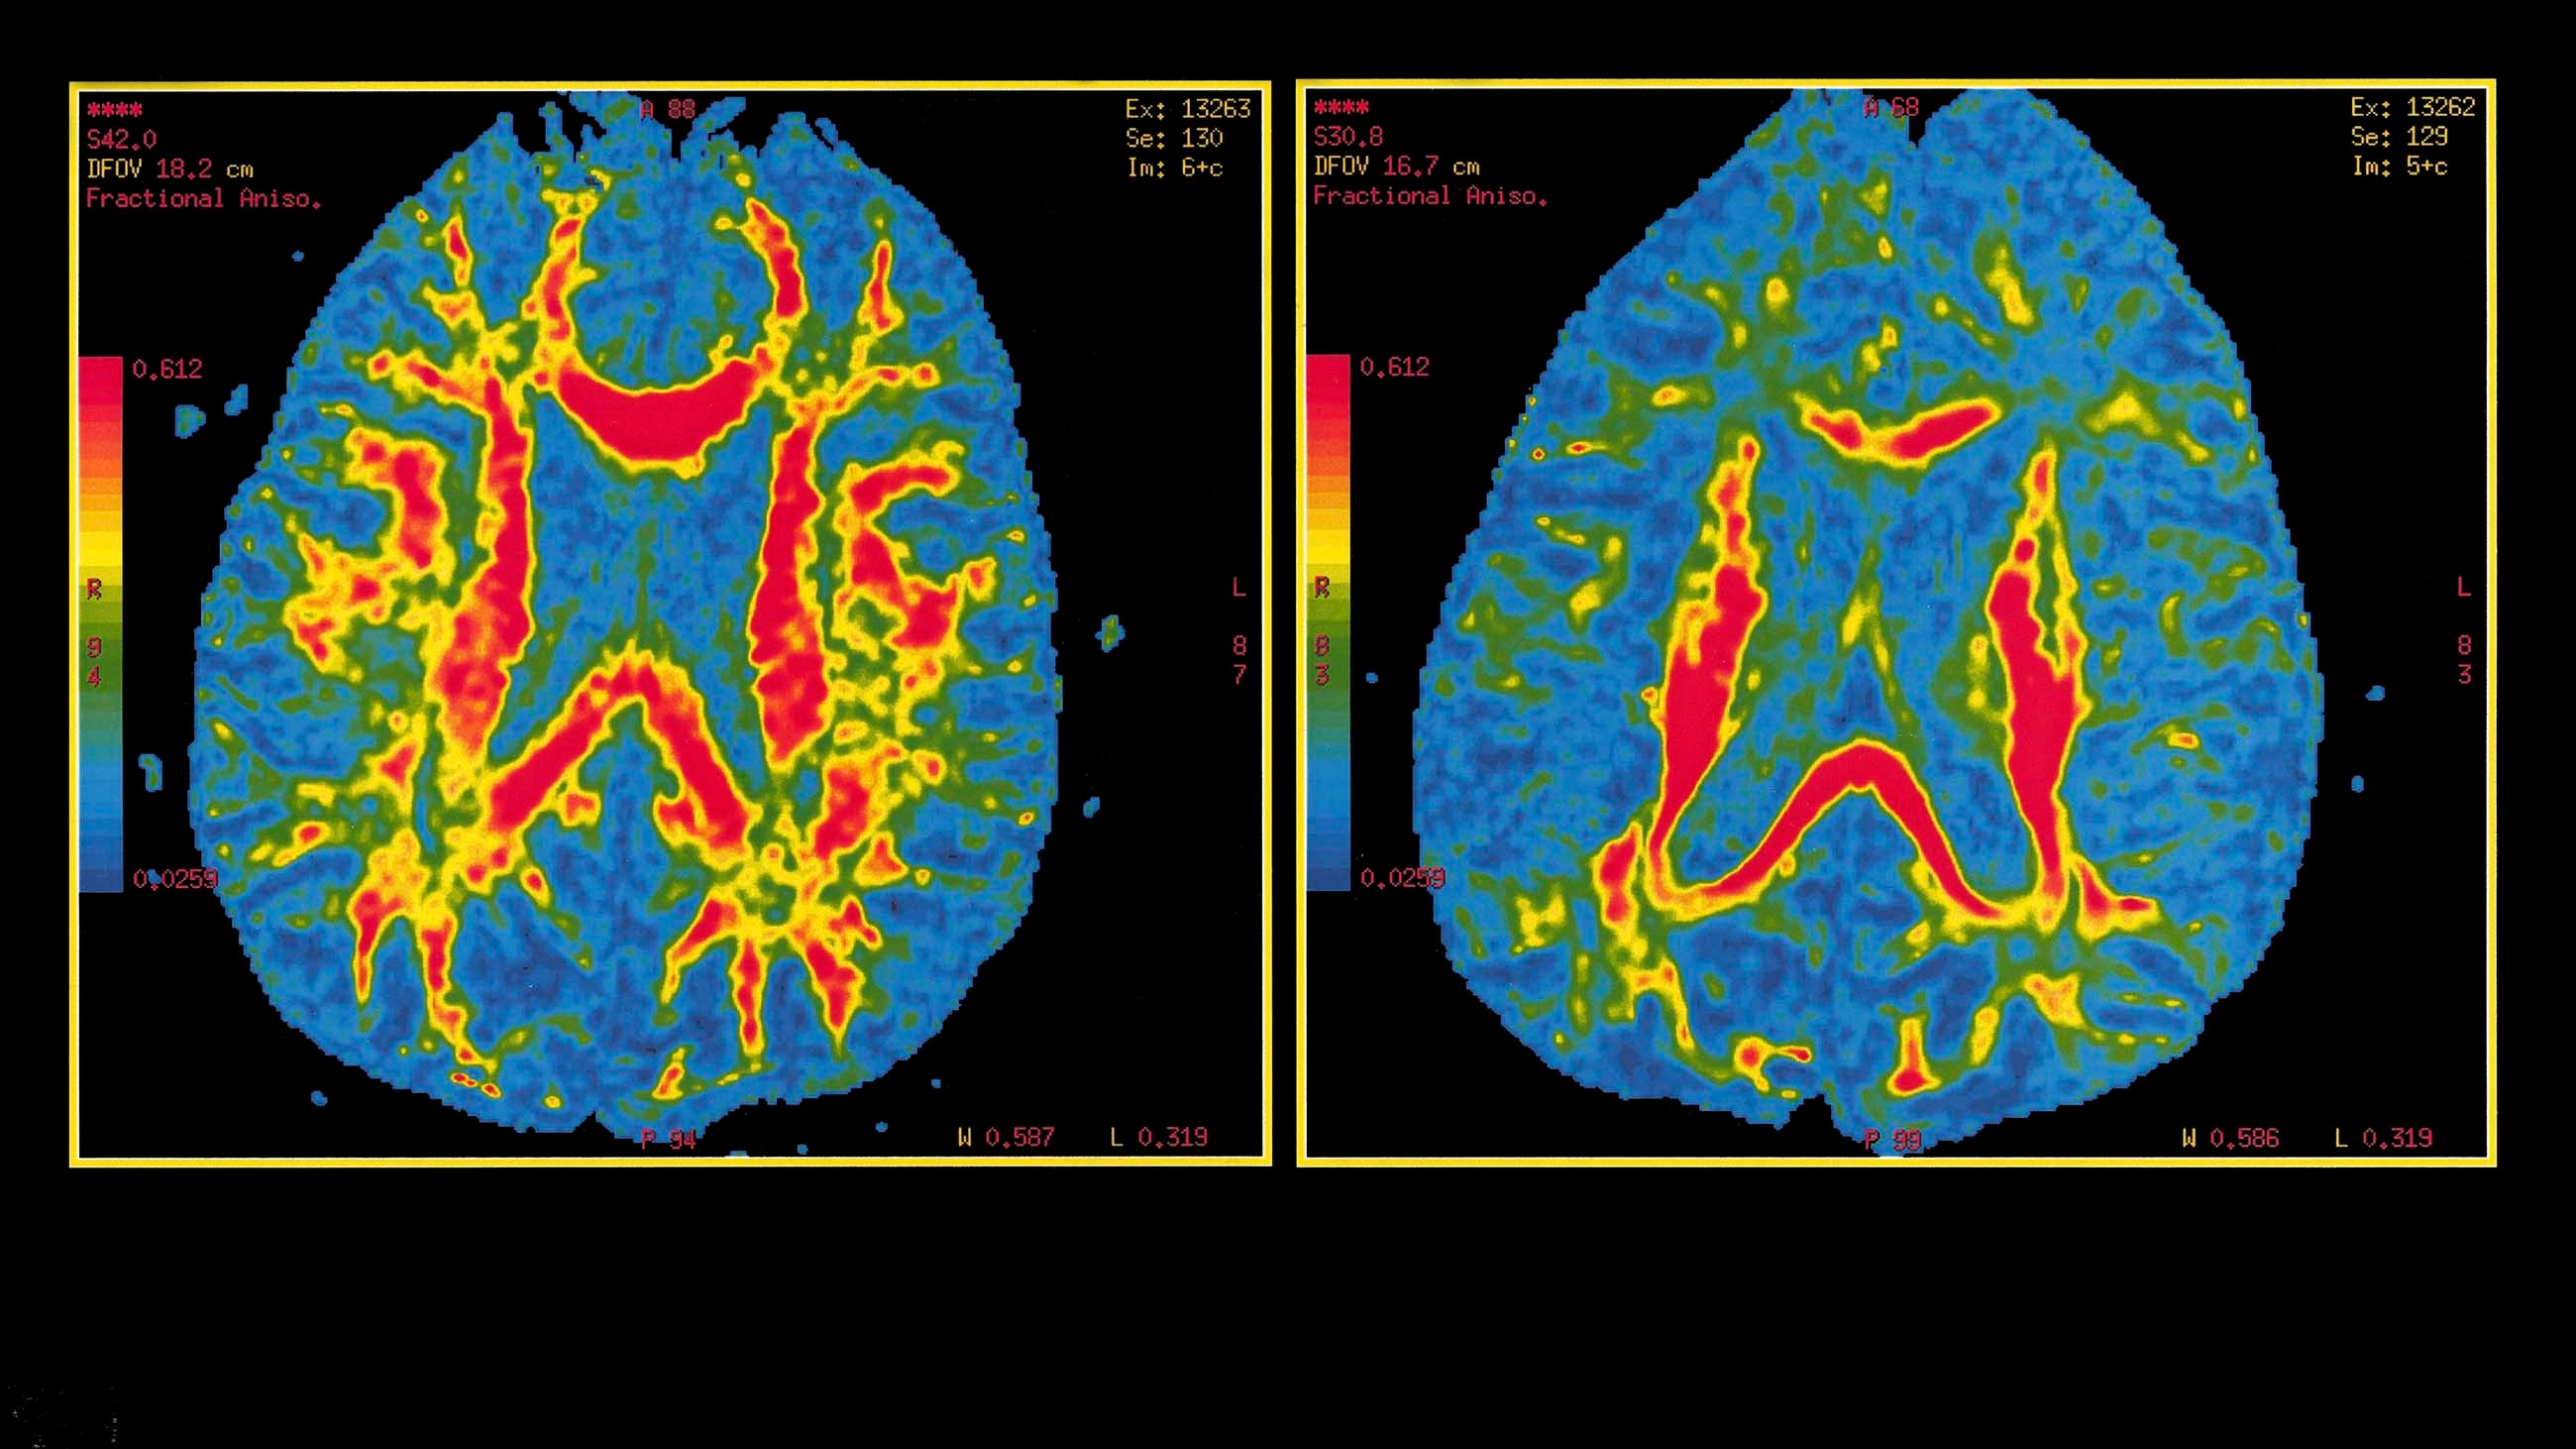

A.I. in Alzheimer’s disease in 2022

Early detection tools are more needed than ever for AD

I’m not a medical professional, but I am getting a bit worried about Long-covid’s impact on dementia and Alzheimer’s disease (AD). Artificial Intelligence may become more important in…